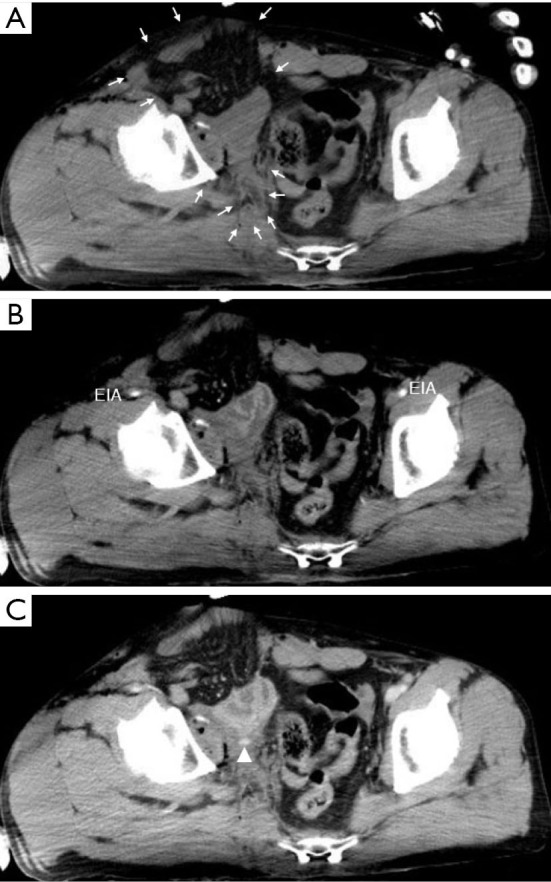

Case description: A healthy 41-year-old man presented with an open pelvic ring fracture and a laceration in the lower abdomen sustained at an ironworks. His hemodynamic status was unstable. Pelvic ring stabilization with an external fixator, ligation of the median sacral and bilateral internal iliac arteries, partial resection of the ileum, appendectomy, and intra-abdominal pelvic packing were performed. Seven days after the injury, he developed a single spike fever of 39.8 ℃ with a significant pus discharge from the open wound around his groin. A computed tomography scan revealed an accumulation of gas around the sacroiliac joint, in the abdominal cavity, and the adductors and gluteus maximus muscles caused by non-clostridial gas gangrene. We performed surgical debridement three times and initiated vancomycin administration. Hyperbaric oxygen therapy was also initiated as an adjunctive therapy. The patient could walk with a cane 5 months after the injury.